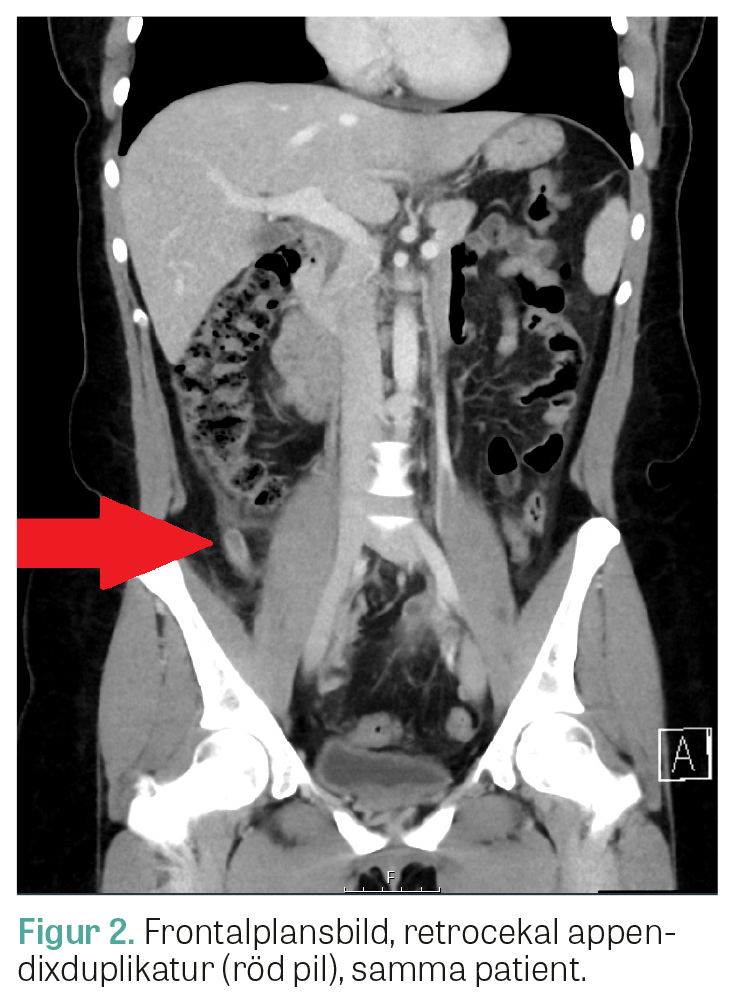

2 dagar senare sökte patienten till en akutmottagning med förvärrade smärtor som hade blivit tydligare lokaliserade till höger i nedre delen av buken. Patienten hade fortsatt NEWS 0 poäng. CRP hade däremot stigit till 38 mg/l. LPK var 11 × 109/l. Buken palperades med lokal peritonit i höger fossa. Akutläkaren remitterade patienten till en akut gynekologisk undersökning. Bedömningen var att patienten inte hade någon påvisbar gynekologisk åkomma, och symtombilden tolkades som en kirurgisk buk. En datortomografi av buken beställdes, och patienten återvände efter denna till akutmottagningen. Datortomografin visade clips från tidigare appendektomi (Figur 1), men även lokal retning i fettvävnaden kring en retrocekal struktur som tedde sig tubulär och väggförtjockad, och radio­logen väckte frågan om abscess, alternativt stumpappendicit (Figur 2). Tanken att det kunde röra sig om en appendixduplikatur väcktes också. Kvinnan lades in fastande med smärtlindring och uppvätskning på en kirurgisk avdelning. De kommande dagarna förbättrades hon kliniskt och laboratoriemässigt. Fallet drogs efter 2 dagar på kirurgklinikens konferens med bildgranskning, och diagnosen appendixduplikatur ställdes baserat på sammanställning av radiologisk och klinisk bedömning samt klinskt förlopp. Patologisk-anatomisk diagnos (PAD) kan inte användas för att säkerställa diagnosen om patienten behandlas konservativt, men eftersom patienten var kliniskt återställd gjordes bedömningen att hon kunde skrivas hem under aktiv exspektans. Patienten informerades om att hon har en appendix­duplikatur som sitter retrocekalt och som bör uppmärksammas vid framtida kontakt med vården.

Den 35-åriga kvinnan i vårt fall verkade, enligt vad som framkom i journalgenomgången, ha en appendixduplikatur av typ B2. Fallet avlöpte väl trots viss fördröjning. Vid hennes appendektomi två år tidigare hade man inte upptäckt den retrocekala duplikaturen, vare sig radiologiskt via ultraljud eller vid laparoskopi. Modaliteten ultraljud var sannolikt suboptimal för att upptäcka en icke-inflammatorisk retrocekal appendixduplikatur. Att tillståndet kan vara svårt att identifiera kan i värsta fall leda till en fördröjning i handläggningen med kliniskt signifikanta konsekvenser på kort och lång sikt, exempelvis allvarliga bukinfektioner, perforationer, abscesser och ileustillstånd såsom beskivits i tidigare fallrapporter ovan. Läkare som arbetar inom akutsjukvård bör vara medvetna om denna sällsynta anatomiska variation samt övriga differen­tialdiagnoser, som stumpappendicit och cekaldiverti­kulit, när patienter som tidigare appendektomerats söker med en appendicitbild på nytt.